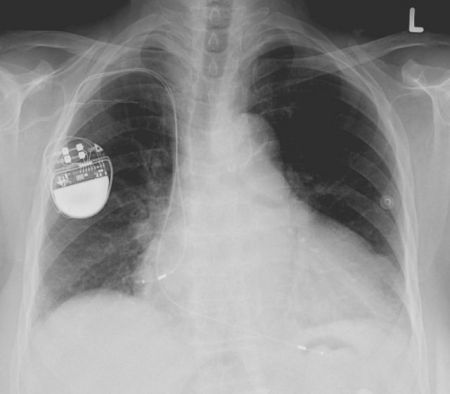

Πολλές ζωές ασθενών με καρδιακή ανεπάρκεια υπόσχεται να σώσει ένα νέο φάρμακο, το οποίο, σύμφωνα με τους ειδικούς, δίνει καλύτερα αποτελέσματα από όλες τις υπάρχουσες θεραπείες. Είναι χαρακτηριστικό ότι οι κλινικές δοκιμές του φαρμάκου με την κωδική ονομασία LCZ696 σταμάτησαν πρόωρα καθώς τα αποτελέσματα ήταν εντυπωσιακά. Συγκεκριμένα από τις δοκιμές που περιελάμβαναν περισσότερους από 8.000 ασθενείς προέκυψε πως το πειραματικό φάρμακο έσωσε 20% περισσότερες ζωές σε σύγκριση με τη συμβατική κύρια θεραπεία για την καρδιακή ανεπάρκεια (εναλαπρίλη).